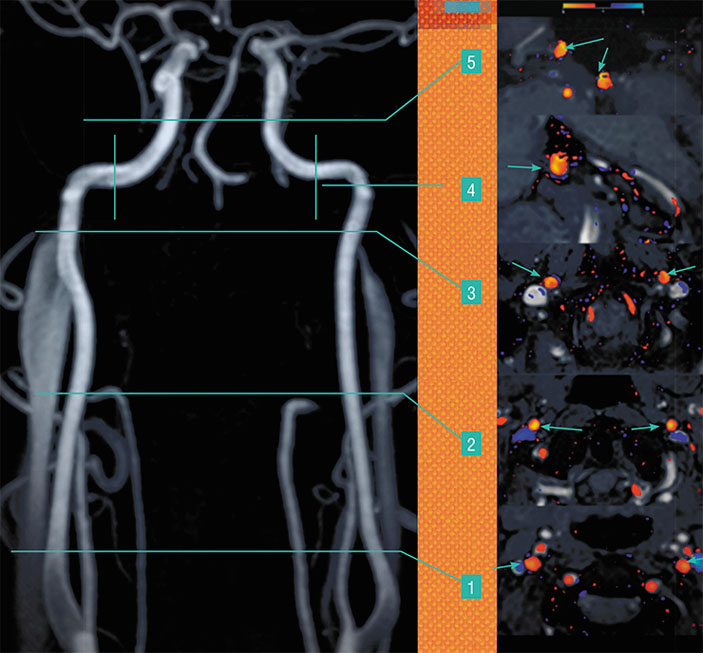

С помощью двумерной фазово-контрастной МР-ангиографии (2D PCA) можно оценить количественные характеристики магистрального кровотока на нескольких уровнях в просвете мозговых артерий. Вверху — визуализация неравномерности распределения скоростных характеристик в просвете разных сегментов внутренних сонных артерий — парных крупных артерий шеи и головы, по данным 2D PCA. Срезы устанавливались перпендикулярно ходу артерий на шейном уровне, с одновременным захватом правого и левого сосуда. В специальной программе полученные томограммы обрабатывались с созданием геометрической фигуры, отграничивающей так называемую область интереса (в данном случае — просвет артерии), внутри которой определялись значения объемной, пиковой и средней скоростей кровотока, а также площадь поперечного сечения сосуда в каждую из фаз цикла сердечной деятельности. Цифрами отмечены уровни визуализации кровотока во внутренних сонных артериях, стрелками — просветы артерий на разных уровнях